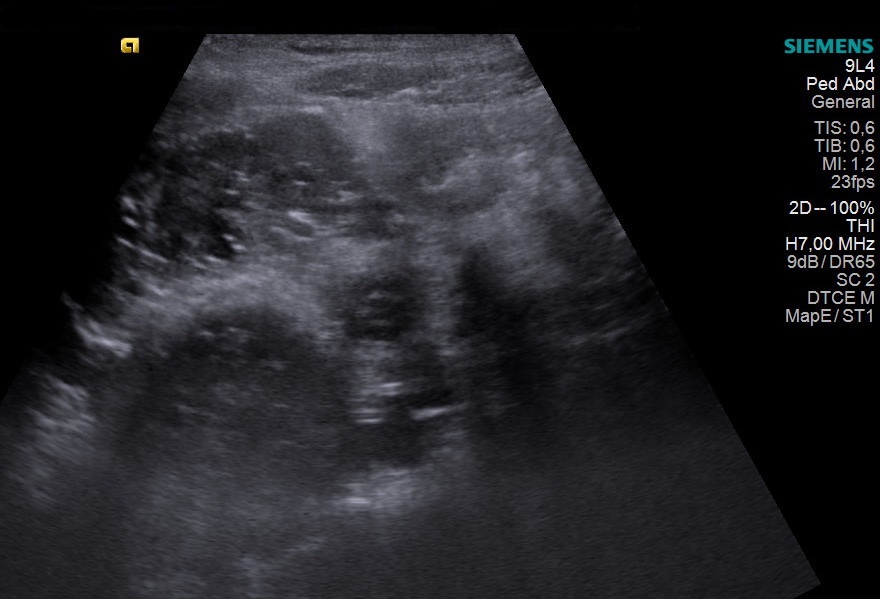

Congenital porto-systemic shunt as a cause of elevated manganese in adults [Oct/Nov 2020]

Case courtesy of Dana Nedelcu MD